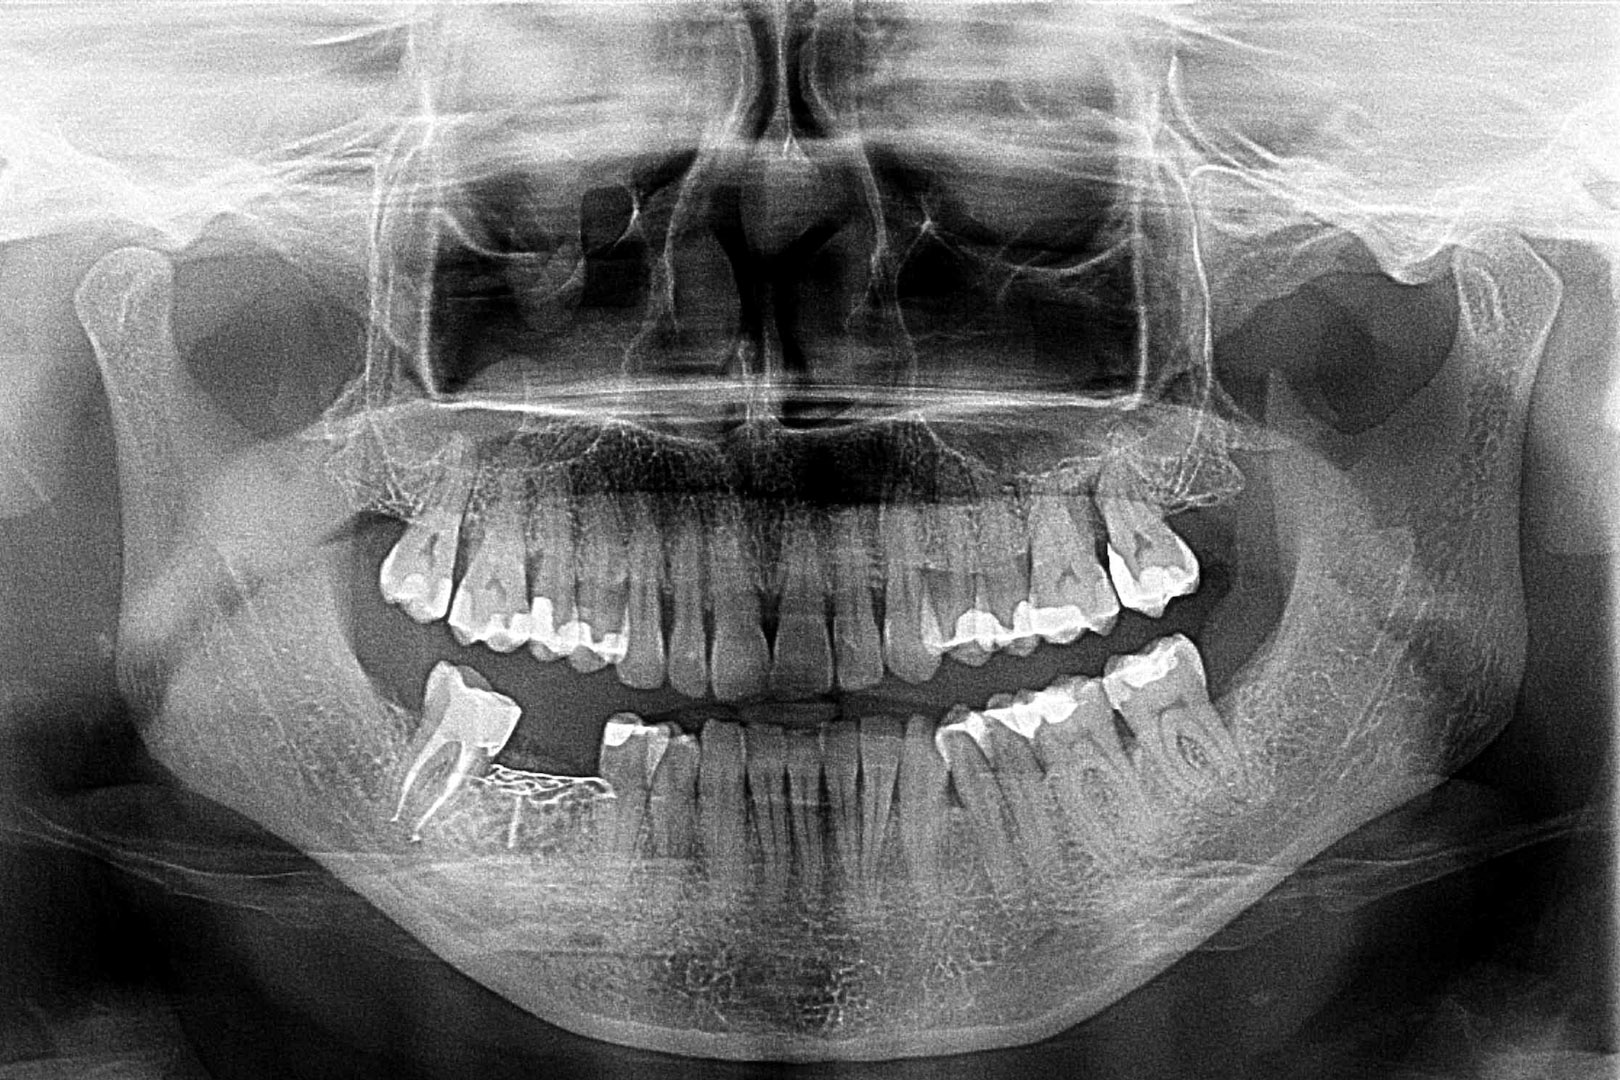

Przed podjęciem leczenia należy określić stopień zaniku kości szczęk oraz żuchwy. W tym celu przeprowadza się badanie kliniczne oraz odpowiednią diagnostykę obrazową pacjenta. Uwzględnia ona zdjęcie panoramiczne OPG jako podstawę dwuwymiarowego obrazowania podłoża kostnego oraz możliwe jest badanie tomograficzne CT lub bardziej precyzyjna tomografia stożkowa CBCT. Opcjonalnie wykorzystywana diagnostycznie tomografia pozwala na bardziej wnikliwą ocenę stopnia zaniku kości w trójwymiarowym, przestrzennym obrazie.